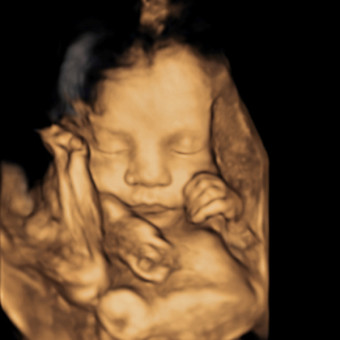

Baby girl coming 2026💕